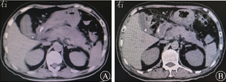

2019年11月26日患者再次出现发热,体温最高达39.6 ℃,伴畏寒、寒战,血压下降,最低血压为76/50 mmHg,药敏试验结果示广泛耐药的肺炎克雷伯杆菌、屎肠球菌和嗜麦芽窄食单胞菌感染,调整抗生素为利奈唑胺(0.6 g/次,2次/d)联合替加环素(50 mg/次,2次/d)抗感染治疗,并予血浆1 000 mL扩容补液,去甲肾上腺素(4 mg/次,2 mL/h)和多巴胺(180 mg/次,10 μg·kg-1·min-1)升压治疗,患者血压恢复至123/80 mmHg。经多学科会诊后考虑胰周假性囊肿出血后合并感染,治疗仍以抗感染和胰周引流为主,调整抗生素为头孢他啶阿维巴坦钠(2.5 g/次,3次/d)和利奈唑胺(0.6 g/次,2次/d),2019年12月2日腹部CT检查示胰周积液和胰周脓肿腔仍存在(图5A),并于2019年12月9日在X线引导下循胃体后壁窦道处,置入双猪尾长7 cm、直径7 F的塑料支架,支架置入后胃腔可见胰周脓液溢出,后患者体温逐渐下降,12月13日CT检查示胰周积液和胰周脓肿腔逐渐缩小(图5B)。患者于2020年1月13日腹部CT检查示胆总管下段轻度扩张,胆总管下段结石,于1月19日行内镜逆行胰胆管造影术(endoscopic retrograde cholangiopancreatography,ERCP)、胆管支架置术和胰管支架置入术(图6),术后逐渐开放饮食并于2020年1月23日出院。2020年3月26日拔除胃内支架和胆胰管支架,至截稿患者病情稳定。

图5 双猪尾支架置入前后计算机断层扫描检查结果

A 2019年12月2日检查结果示双猪尾支架置入前胰周积液和胰周脓肿腔仍存在 B 2019年12月13日检查结果示双猪尾支架置入后胰周积液和胰周脓肿腔缩小